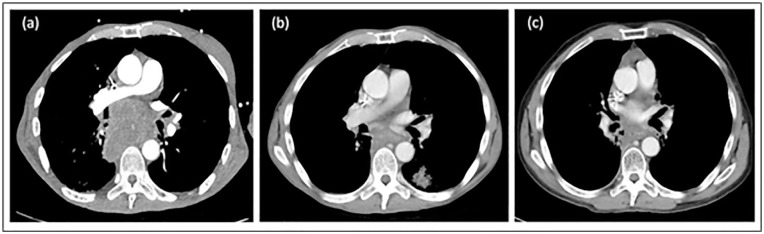

Abstract Image